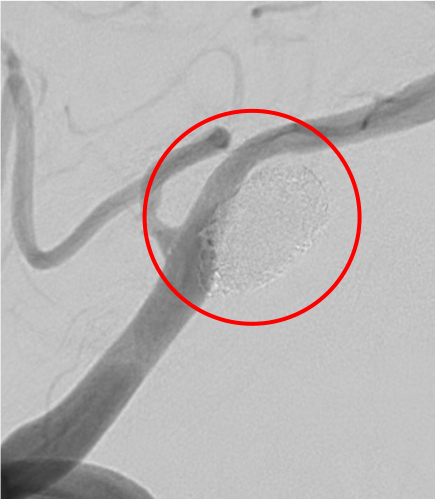

術前の造影写真です。〇内に脳動脈瘤が造影されています。

術直後の造影写真ではまだ脳動脈瘤は造影されています。

半年後の造影写真では脳動脈瘤は完全に消失しています。